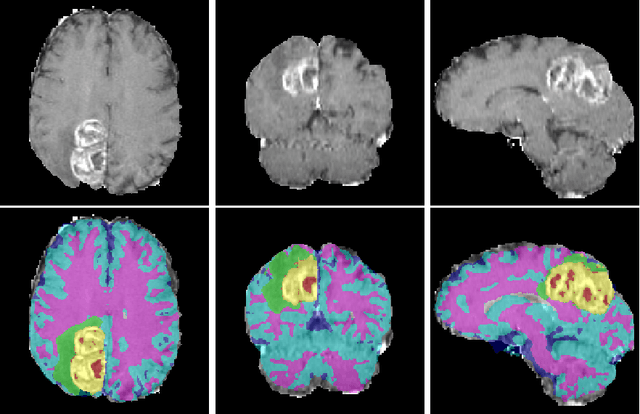

Abstract:We propose a segmentation framework that uses deep neural networks and introduce two innovations. First, we describe a biophysics-based domain adaptation method. Second, we propose an automatic method to segment white and gray matter, and cerebrospinal fluid, in addition to tumorous tissue. Regarding our first innovation, we use a domain adaptation framework that combines a novel multispecies biophysical tumor growth model with a generative adversarial model to create realistic looking synthetic multimodal MR images with known segmentation. Regarding our second innovation, we propose an automatic approach to enrich available segmentation data by computing the segmentation for healthy tissues. This segmentation, which is done using diffeomorphic image registration between the BraTS training data and a set of prelabeled atlases, provides more information for training and reduces the class imbalance problem. Our overall approach is not specific to any particular neural network and can be used in conjunction with existing solutions. We demonstrate the performance improvement using a 2D U-Net for the BraTS'18 segmentation challenge. Our biophysics based domain adaptation achieves better results, as compared to the existing state-of-the-art GAN model used to create synthetic data for training.